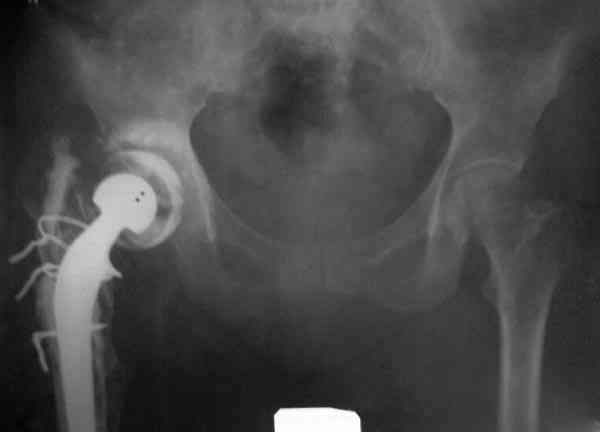

После обработки ацетабулярного компонента, ещё в мягком цементе в полости вертлужной впадины головкой бедренного компонента сделана выемка для головки, чтобы свежий цемент не прилипал к головке. Головку бедренного компонента завернул обычной стерильной фольгой, которую после образования выемки отлепил от головки.

Для спейсера в бедро использовал старый длинный бедренний компонент меньшего диаметра, облепленный со всех сторон цементом с антибиотиком.

Наглухо ушитая рана с дренажом зажила первично, после чего с больной потерял контакт, и только недавно, через 8 лет я осмотрел её. Она без проблем нагружает на конечность и передвигается с помощью трости. От окончательной операции по реконструкции отказывается, довольная результатом.

Имеются литературные данные, когда спейсер держали не более 6 месяцев, но этот случай бьет все рекорды, может быть для наших людей, обременных финансовыми трудностями, нужна другая шкала оценки сроков нахождения спейсеров.

и последние снимки.